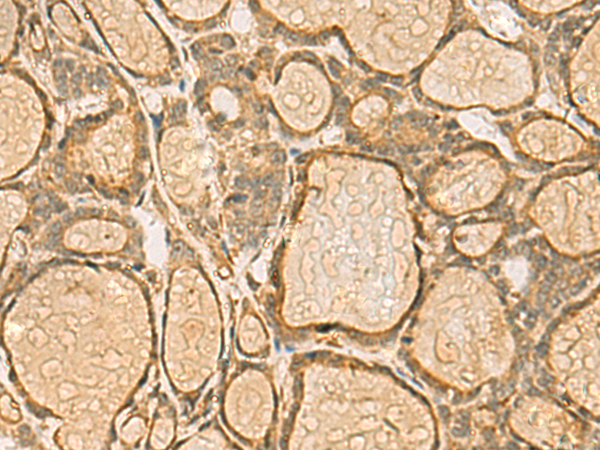

分类: 科研抗体货号: P10359别名: GODZ; DHHC3; DHHC-3; ZNF373应用: IHC反应种属: Human, Mouse